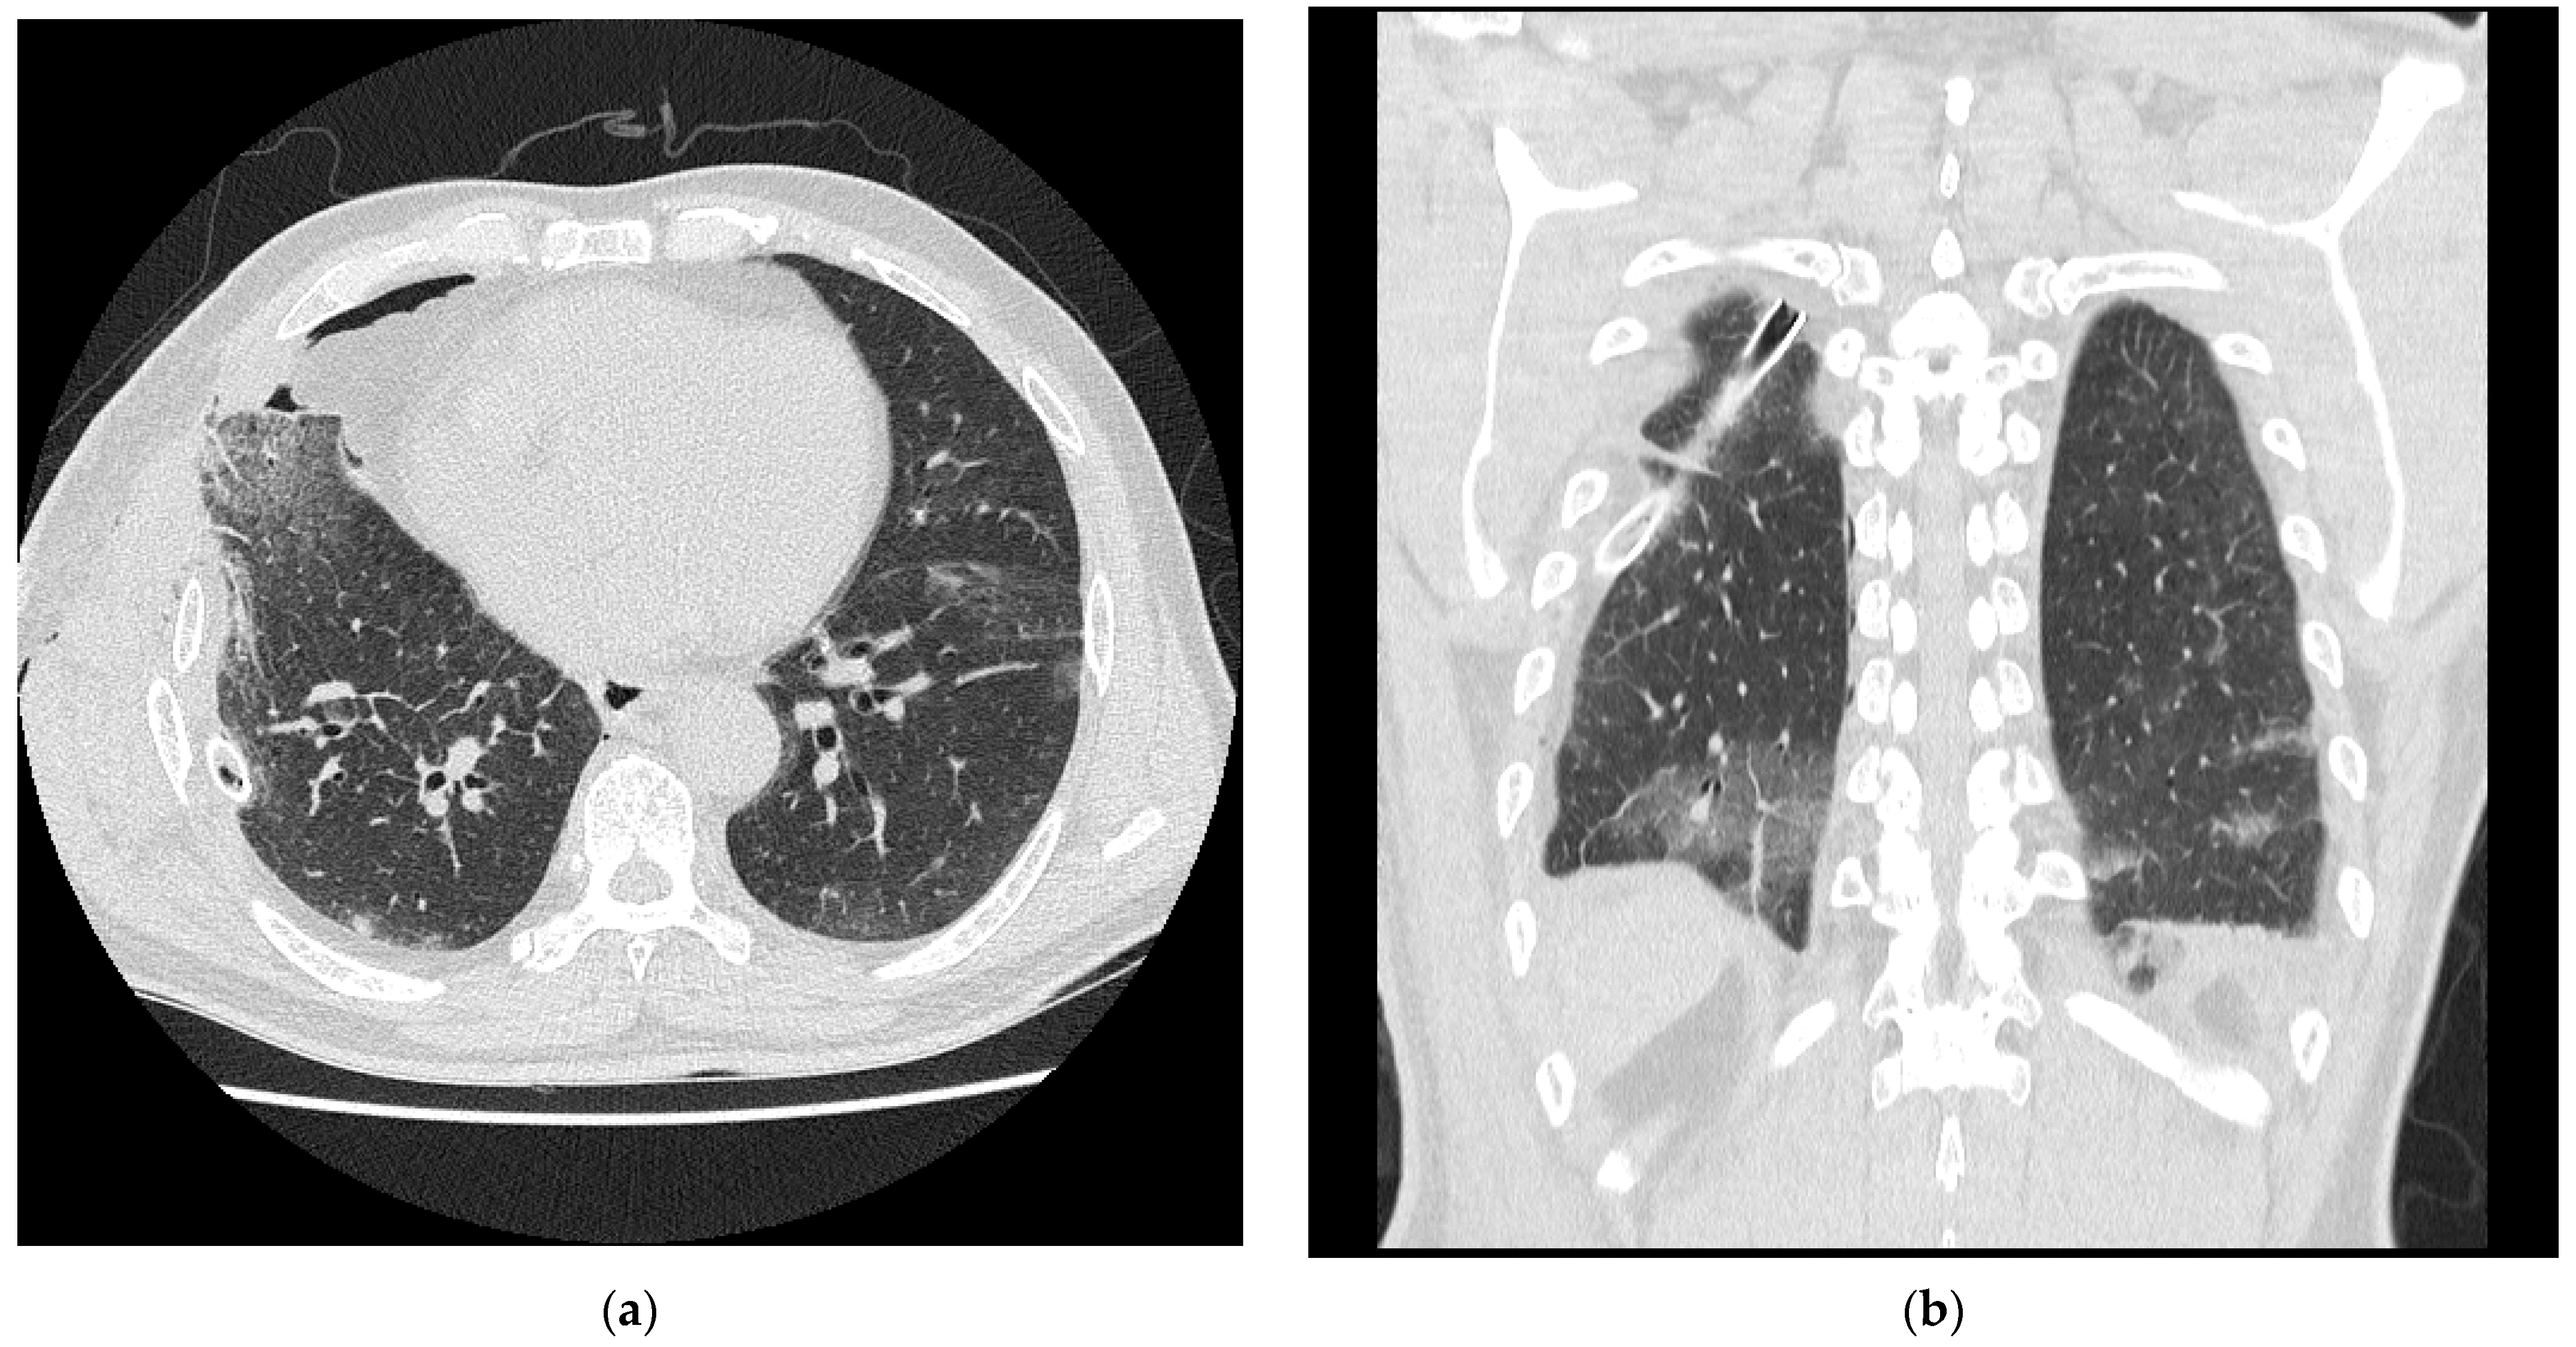

2. Case Presentation